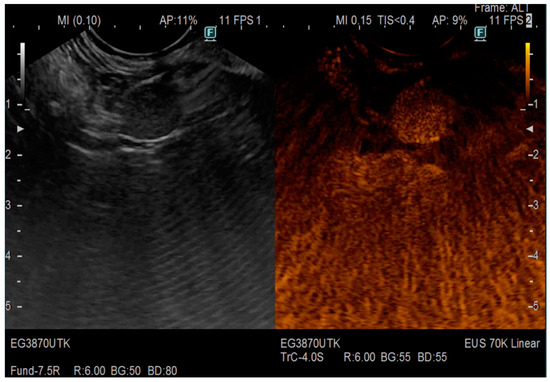

| Pathology | Examination | Features |

|---|---|---|

| Pancreatic cancer | EUS | Hypoechoic mass with irregular borders, dilatation of the proximal PD |

| EUS elastography | The mean SH value (the overall hardness of a lesion) is lower than 80 | |

| CE-EUS | Iso-enhancement or hypo-enhancement, arterial irregularity and absent venous vasculature within a mass | |

| Chronic pancreatitis | EUS-elastography | Hyperechoic foci with shadowing and MPD calculi and lobularity with honeycombing |

| CE-EUS | Hyper-enhanced lesions with preserved architecture | |

| PNETs | CE-EUS | Hypervascularization, a low microvessel architecture |

| Autoimmune pancreatitis | EUS | Diffuse hypoechoic areas, diffuse enlargement, bile duct wall thickening and peripancreatic hypoechoic margins |

| CE-EUS | Hypervascularization, focal or diffuse iso-enhancement | |

| EUS-elastography | Homogeneous stiffness of the whole organ |